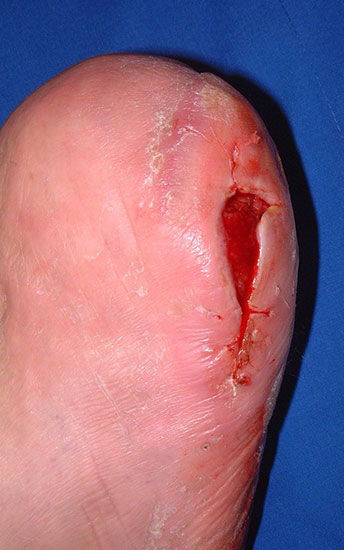

• Lokale Osteomyelitiden mit Knochennekrose und Weichteilbeteiligung (Abb. 50).

Das Ausmaß der Knochenresektion ergibt sich aus der Defektgröße bzw. aus der Ausdehnung der Osteomyelitis 3 (Abb. 52). Eine totale Kalkanektomie ist problematisch, weil danach die Leitungsbahnen unmittelbar dem Körpergewicht ausgesetzt sind.

Die Operationswunde bleibt bis Einsetzen einer sauberen Gratulation offen. Anschließend erfolgt die Sekundärnaht. Das infektauslösende Fersenulkus heilt meist spontan, wenn es nicht bereits beim Primäreingriff exzidiert wurde (Abb. 56).